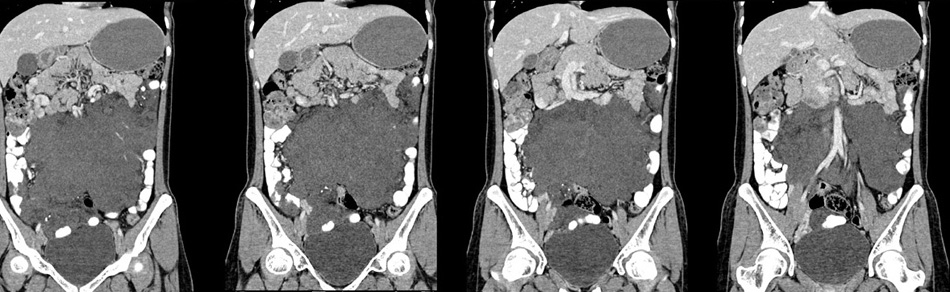

女性,28岁,停经3月,腹部膨隆1月,产前检查发现腹部占位

{肿块中心ct值27hu,增强后,动脉期、门脉期均无明显强化)

患者手术病理:腹腔囊性淋巴管瘤,象这样充满整个腹腔的的确很少见